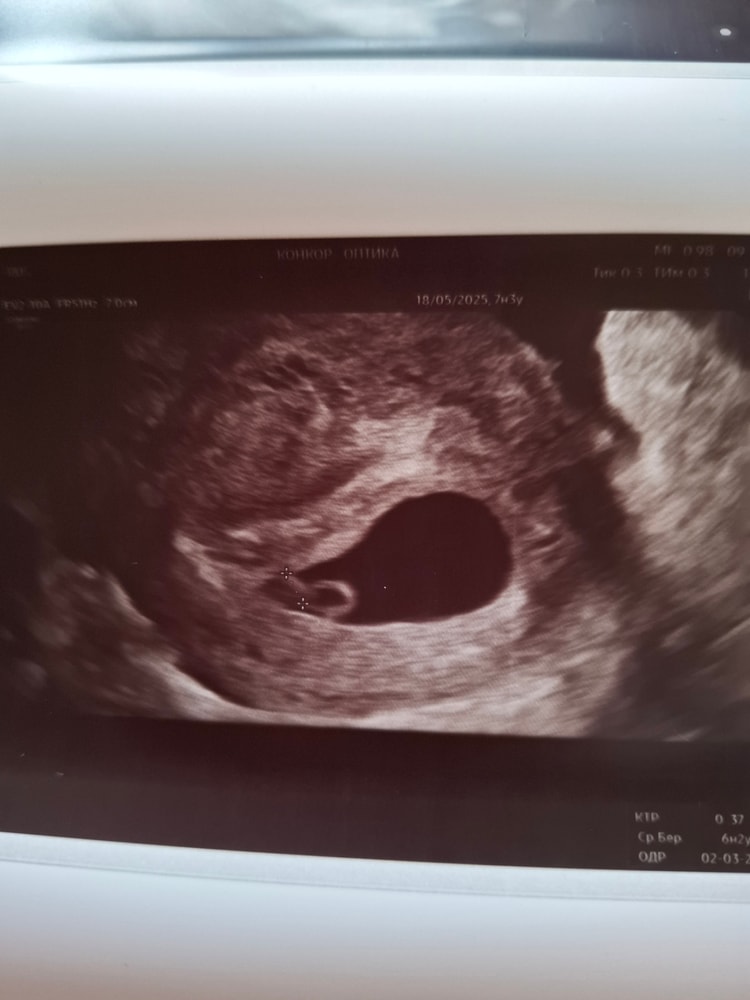

Врач ошиблась с размером свд?

Так срок ставят по размеру эмбриона,а не по пя,рост и размер пя зависит от роста хгч,у вас скорее всего хгч очень быстро рос, поэтому и пя большое уже,но это наооброт хорошо,чем когда пя маленькое,просторный домик у эмбриона,судя по фото не ошиблись,оно у вас и есть большое и это не плохо,а наооброт хорошо,со средним ростом хгч с таким ктр пя 20 мм,с быстрым и 35 может быть,никак и ни на что не влияет

Изображение Свд 29мм явно не 6-7недель. По таблицам в интернете это 8-9 недель